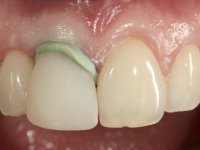

The treatment began with the placement of an intraradicular post and the creation of a new composite resin restoration. This procedure was performed with a surgical approach that allowed the remaining margins to be completely exposed, which were shown to be at a very infra-gingival level. Simultaneously, the periodontal pocket was curetted and root scaling and root planning of adjacent teeth were performed. Two months after this first intervention, the making of the crown began. A pre-print on silicone was performed to make a temporary crown with dual-cured composite resin. Gingival retraction was performed using the technique of kaolin paste compressed by the provisional crown. The impression was made using the double-mix technique with double viscosity with quick-setting silicone. In the laboratory, a crown with a ceramic-coated Zr infrastructure was made. The crown slightly overlapped tooth 12, allowing a dimensionally mimicry of the symmetrical tooth. Its fit was confirmed and approved by the patient; it was definitively cemented with resin-reinforced glass ionomer cement.